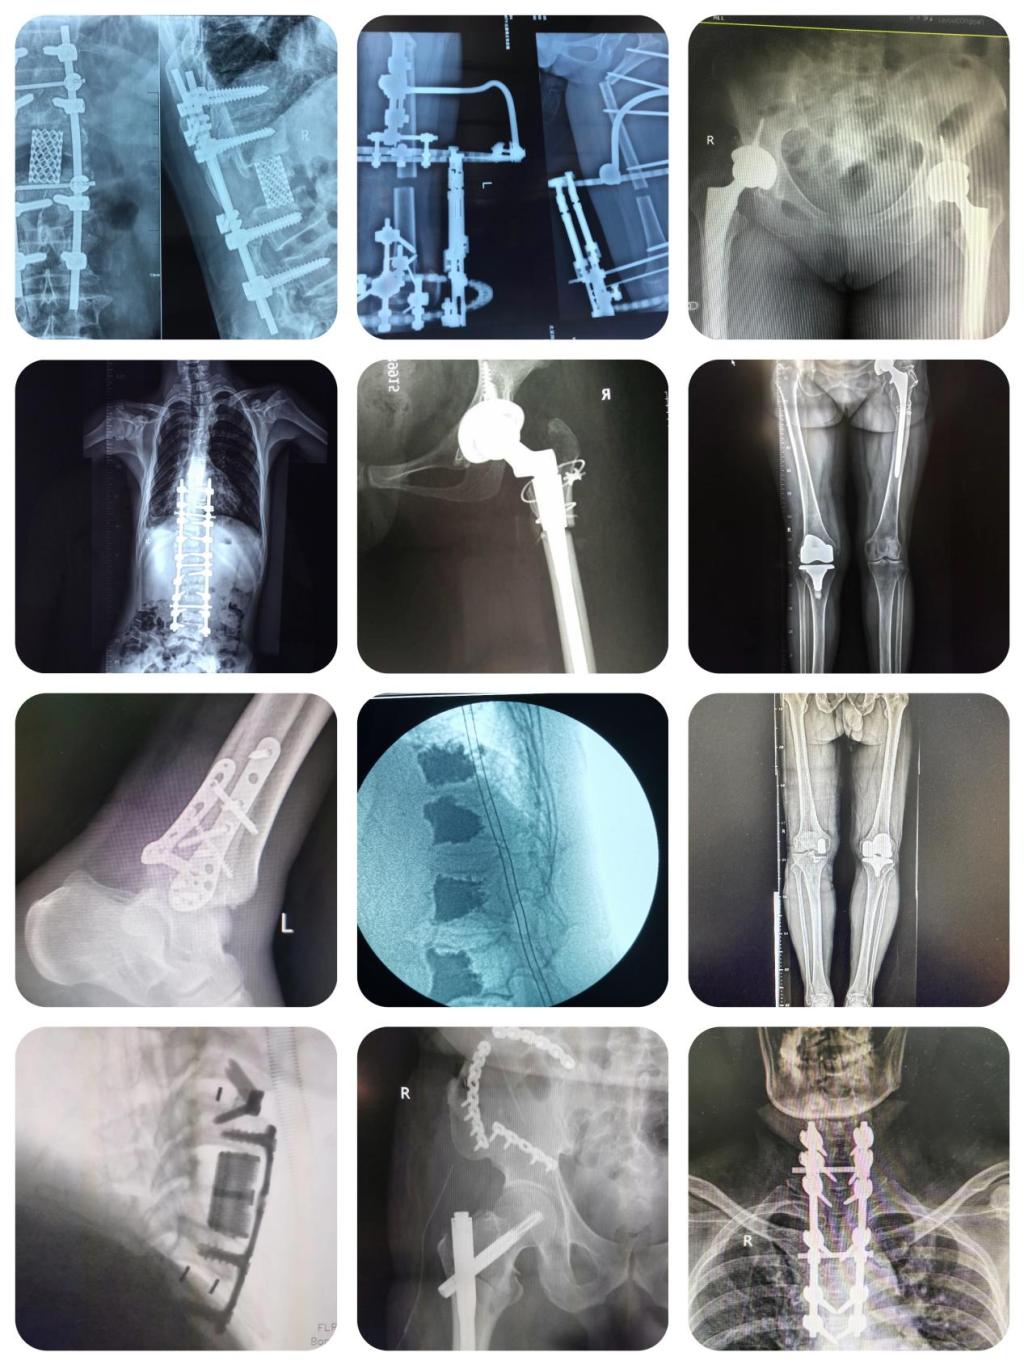

近四年,我院骨科中心创伤与手外科病区不断打破高龄手术禁区,已经为400余名80岁以上高龄的老年患者成功进行手术治疗,“置换”了人生。其中年龄最大的患者102岁,90岁以上的老年患者达60余人,95岁以上患者12人。手术不仅让近百岁的老人在人生马拉松上再获“补给”,更是为他们安详度过金色晚年注入了新的活力。

创伤与手外科病区拥有医护人员共34名,其中高级职称9名,硕士及博士生导师6名。科室在张纯主任及王伟卓副主任的引领下,在高龄关节翻修、微创关节置换术、复杂脊柱脊髓损伤、颈椎病、微创椎间盘突出、多发性骨折等领域,成功的开展了深入卓有成效的临床研究与临床实践,逐渐形成学术特色。